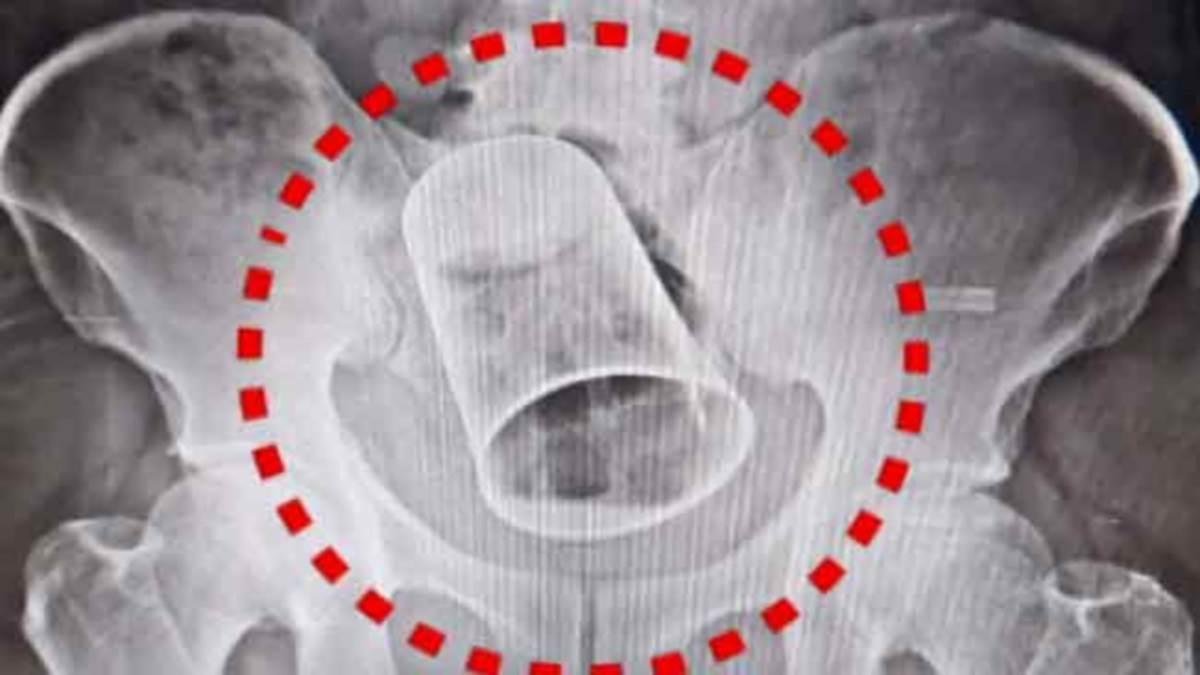

After the man’s pain became unbearable, he reached MKCG Medical and told the doctors about the incident. After X-rays, the MKCG medical team operated on him on 19 August.

The medical team first tried to remove the glass through the anus, but after failing, it was taken out by abdominal surgery. After the operation, the health condition of the person is reported to be fine.